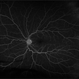

- Condition/keywords

- retinal ischemia

- This patient with long standing diabetes has peripheral non-perfusion.